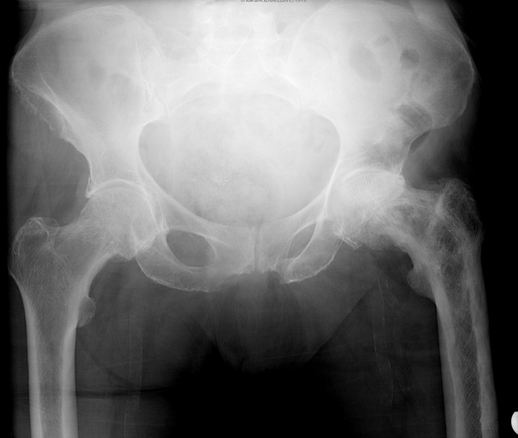

Diagnosis?

Paget’s

Note lytic, sclerotic and mixed lesions in bone, representing all 3 phases of Paget’s disease

Increased bone turnover due to increased osteoclastic bone resorption and abnormal bone remodeling